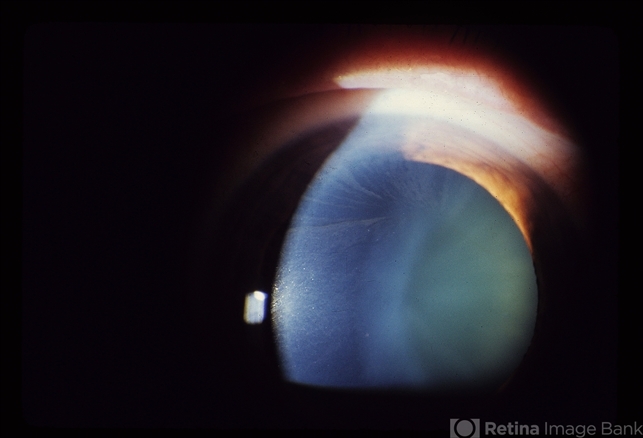

- Fabry disease, cornea verticillata

- Photo slit lamp biomicroscope

- A carrier of Fabry's disease who demonstrates cornea verticillata.